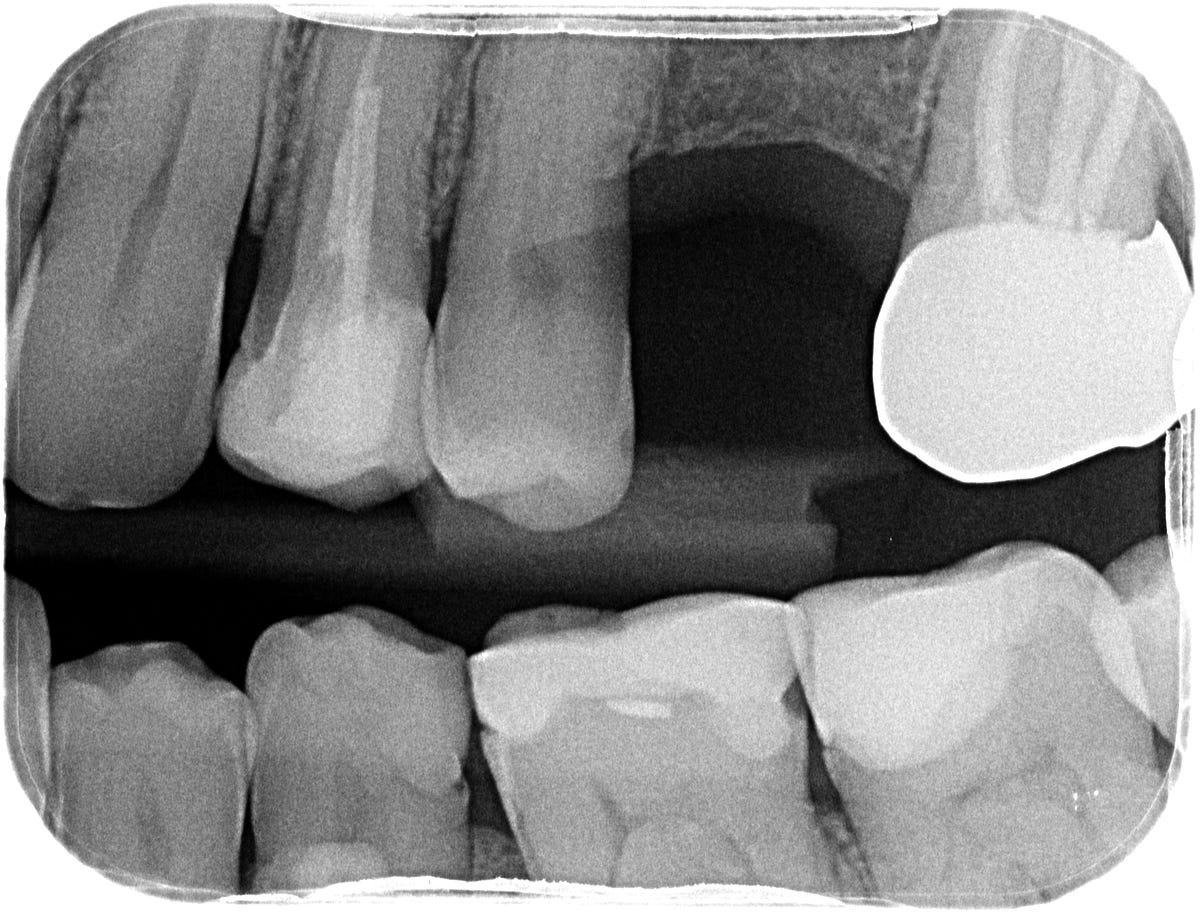

Zirconia Crown Radiograph Zirconia Crown On Xray Similar, excellent/good occlusal and proximal contact points were assessed in more than 90% and 80% of cases, respectively,. Zirconia crowns offer a number of advantages, including durability. More recently, prefabricated zirconia crowns (zcs) for permanent molars have been introduced as an aesthetic alternative to sscs. The answer can be yes or no depending on what the crown is made of,. Zirconia Crown On Xray.

Zirconia Crown X Ray Zirconia Crown On Xray Similar, excellent/good occlusal and proximal contact points were assessed in more than 90% and 80% of cases, respectively,. The monolithic zirconia crown had no detectable adverse effects on the periodontal. When using zirconia for a restoration, respondents choose it to restore natural teeth (99%) more often than implants (76%). Restoration removal or replacement and shade matching and translucency were the. Zirconia Crown On Xray.